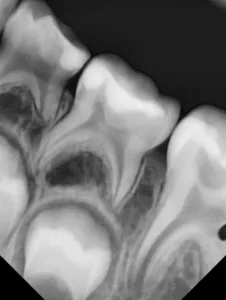

Bei routinemäßigen Röntgenkontrollen ergeben sich manchmal Zufallsbefunde unklarer Genese. So stellt sich beispielsweise bei der Betrachtung der Abbildung 1 die Frage, wie sich ein Zahnhartsubstanzdefekt so schnell entwickeln konnte. Ein weiteres Röntgenbild (Abb. 2), das vor dem Zahndurchbruch aufgenommen wurde, zeigt jedoch, dass es sich in diesem Fall nicht um Karies, sondern um die sogenannte präeruptive intrakoronale Resorption (PEIR) handelt. Für diesen Befund finden sich in der Fachliteratur auch noch andere Bezeichnungen wie „idiopathic external resorption of unerupted permanent teeth“ [1], „intra-follicular caries“ [2], „radiolucent lesions resembling caries“ [3], „occult caries“ [ 4] oder „pre-eruptive caries“ [5].

während des Durchbruchs des Zahnes 36.

Das fünfjährige Mädchen stellte sich 2017 zur jährlichen Routinekontrolle vor. Im Rahmen der Untersuchung wurden Röntgenaufnahmen der Milchmolaren gemacht (Abb. 2). Der klinische und radiologische Befund der vor uns früher gelegten Kompositfüllungen war gut, es wurde allerdings eine PEIR an den noch nicht durchgebrochenen ersten bleibenden Molaren festgestellt (Abb. 2). Den Eltern wurde empfohlen, sich unverzüglich bei Beginn des Durchbruchs der ersten Molaren erneut zur Behandlung vorzustellen. Ein Jahr später erschien die junge Patientin schmerzfrei zur Kontrolle. Der Zahn 36 war noch teilweise mit Gingiva bedeckt. Auf einer neuen Röntgenaufnahme (Abb. 1) wurde die PEIR-Läsion mit unveränderter Größe in pulpanahen Bereichen bestätigt (Grad 3 der Läsion nach Seow). Der Zahnschmelz sah intakt aus, es konnte kein pathologischer periapikaler Befund bei den noch nicht ausgewachsenen Zahnwurzeln festgestellt werden. Daraufhin wurden die verschiedenen Behandlungsmöglichkeiten von Fissurenversiegelung bis Vitalerhaltung der Zahnpulpa mit den Eltern des Kindes besprochen.